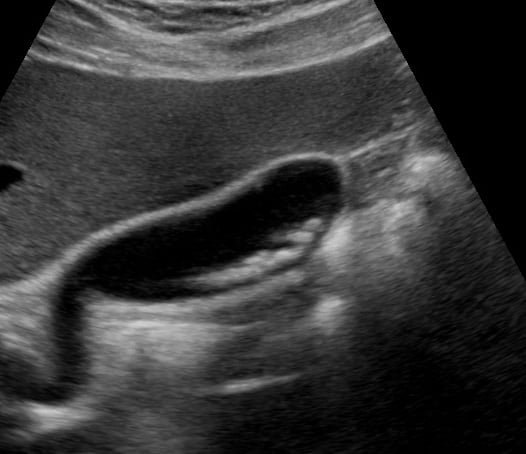

Gallstones are hardened deposits of digestive fluid that can form in the gallbladder, a small organ beneath the liver. In abdominal ultrasound, these concretions appear as hyperechoic structures within the gallbladder lumen, often with posterior acoustic shadowing. Their presence is a common finding during abdominal scans, frequently associated with symptoms like right upper quadrant pain, nausea, and vomiting, particularly after fatty meals.

Medical ultrasound plays a crucial role in diagnosing gallstones and related conditions such as cholecystitis (gallbladder inflammation) or choledocholithiasis (gallstones in the bile duct). Sonographic evaluation helps assess their size, number, and mobility, guiding clinical management and treatment decisions for patients experiencing abdominal discomfort or suspected biliary tract pathology.